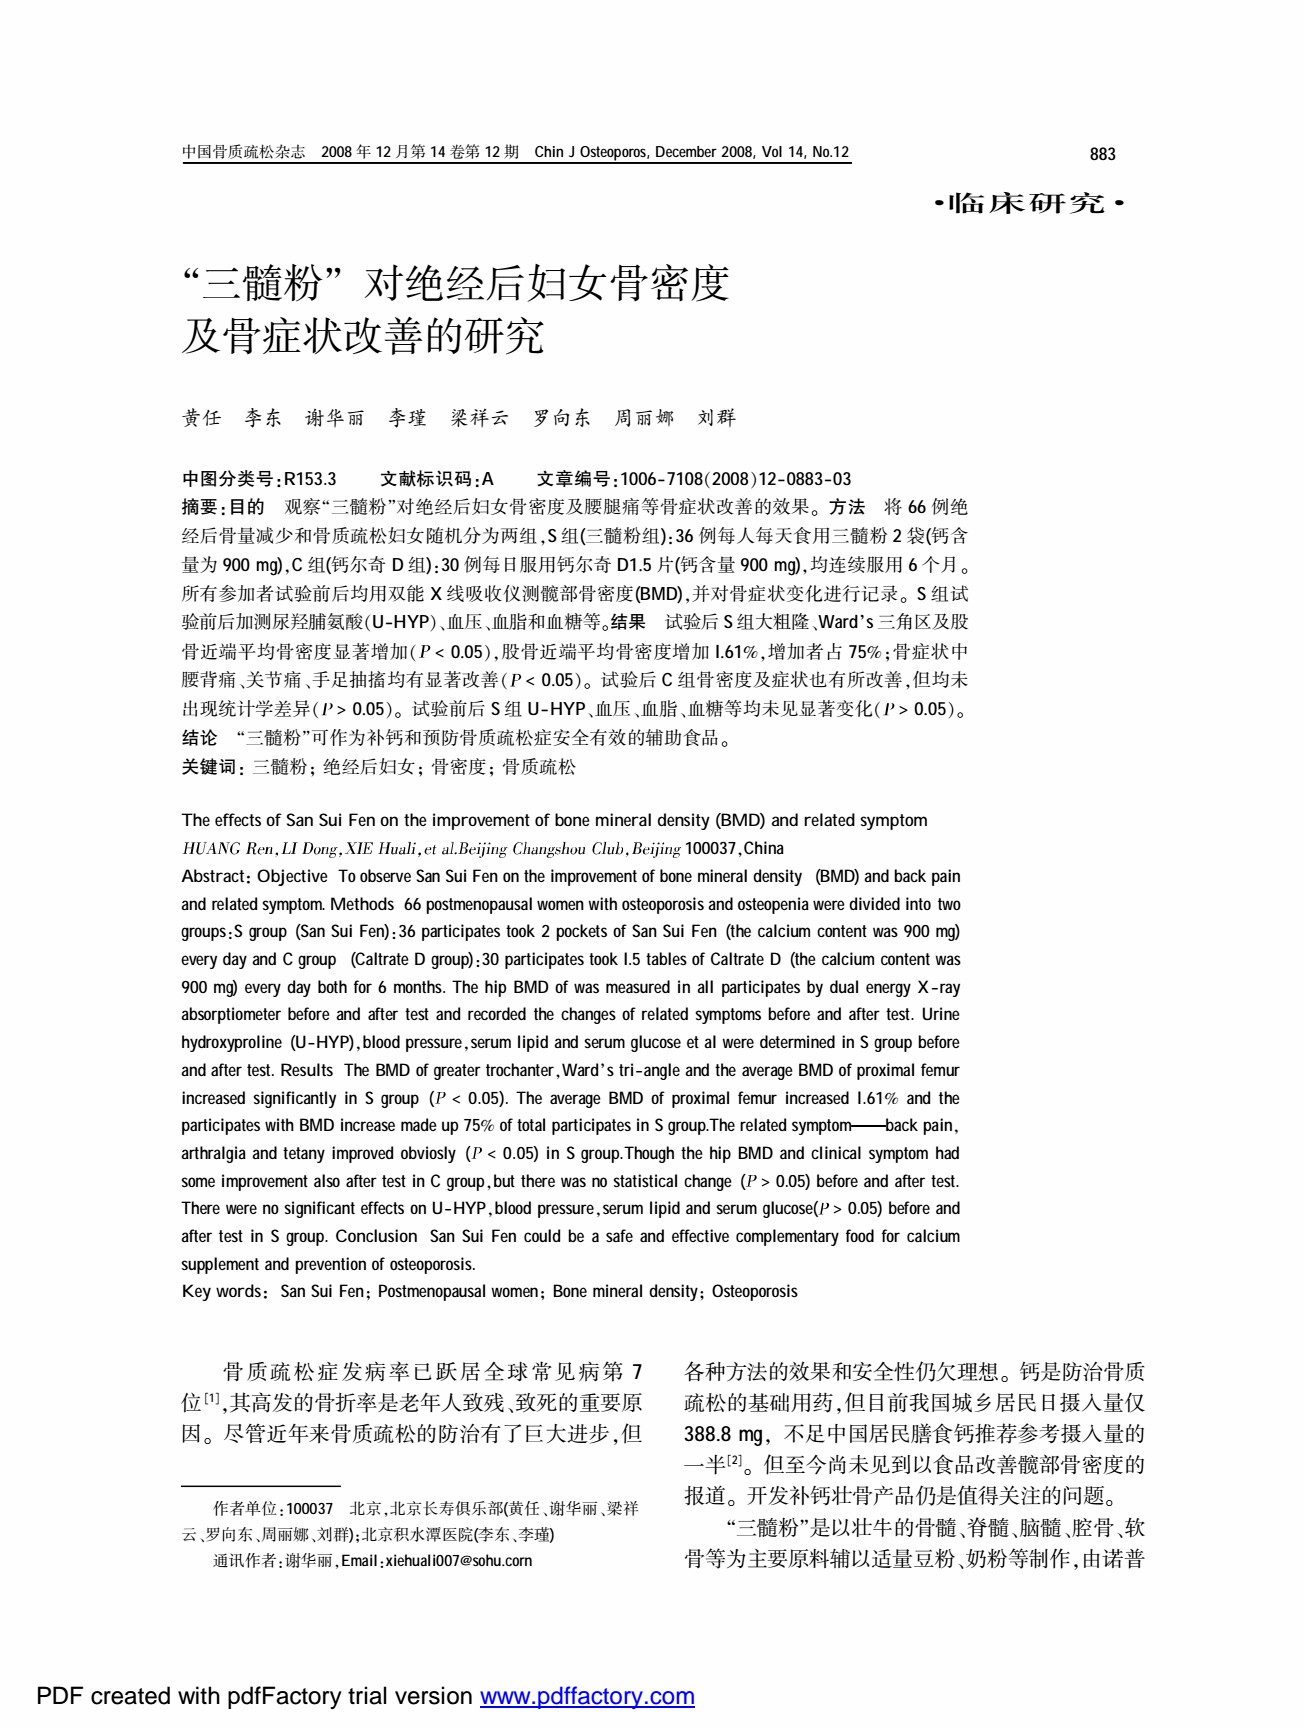

“三髓粉”对绝经后妇女骨密度及骨症状改善的研究

- 金诺三髓粉两次临床试验主研人员

黄任

- 中国老年营养与食品专业委员会委员

- 主任医师

- 中国老教授协会骨质疏松与骨关节病防治专家委员会委员

- 原中国人民解放军全军卫生技术考试命题专家

- 曾获部局级科技进步奖十余次,并获卫生部和国务院嘉奖

- 金诺三髓两次临床试验主研人员

谢华丽

- 全国儿童少年贫血国家标准研制组组长

- 主任医师

- 金诺三髓粉两次临床试验主研人员